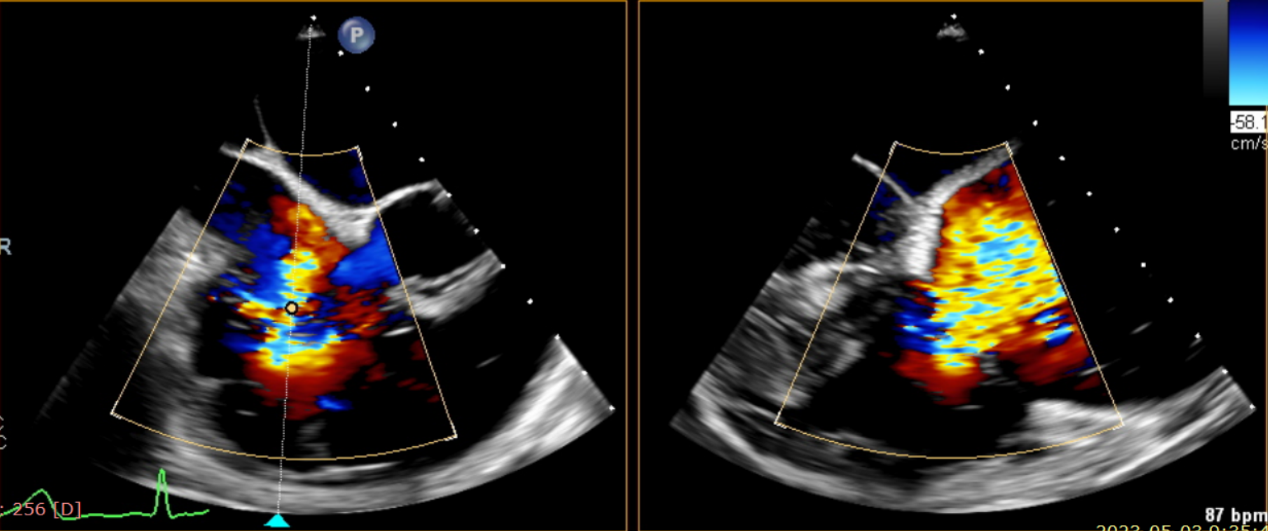

術(shù)前超聲提示大量三尖瓣反流

術(shù)中輸送器在超聲引導(dǎo)下調(diào)整位置

術(shù)后超聲提示無瓣周漏

術(shù)后超聲提示僅殘余輕微瓣周漏